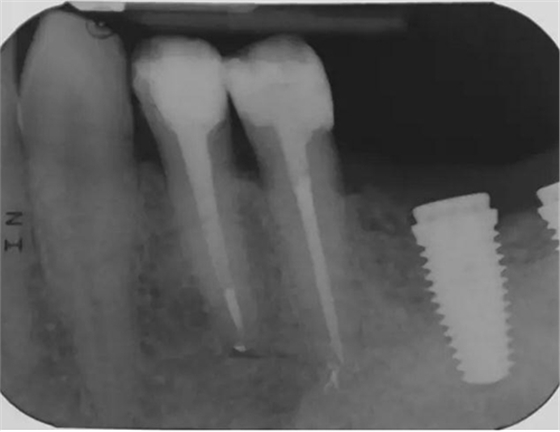

圖4 該病例中,左下4根充失敗,左下5牙髓壞死。兩個牙齒均需要根管治療和修復。

圖5 根管治療術(shù)后。左下4需要使用纖維樁,并用雙固化樹脂粘結(jié)劑粘結(jié)。左下5無需纖維樁。但2個牙齒均需要進行覆蓋牙尖的修復。

圖6 左下4和左下5使用瓷納美通用修復型樹脂及SDR修復后的效果。

圖7 術(shù)后片。左下4重新疏通。根尖4mm牙膠封閉,根管內(nèi)粘結(jié)了纖維樁。左下5根尖有根分叉。在根管冠段,可以樹脂(SDR)進入,輔助固位。